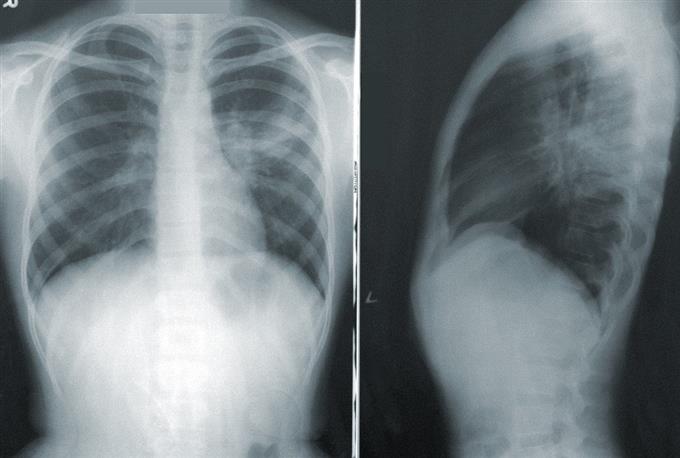

Δυνατότητα να διακρίνεται η πνευμονία από την covid-19

«Για να δούμε τι ξέρεις για τους πνεύμονές σου...» είναι το κεντρικό μήνυμα της ενημερωτικής εκστρατείας που πραγματοποιεί η Ελληνική Πνευμονολογική Εταιρεία (ΕΠΕ)